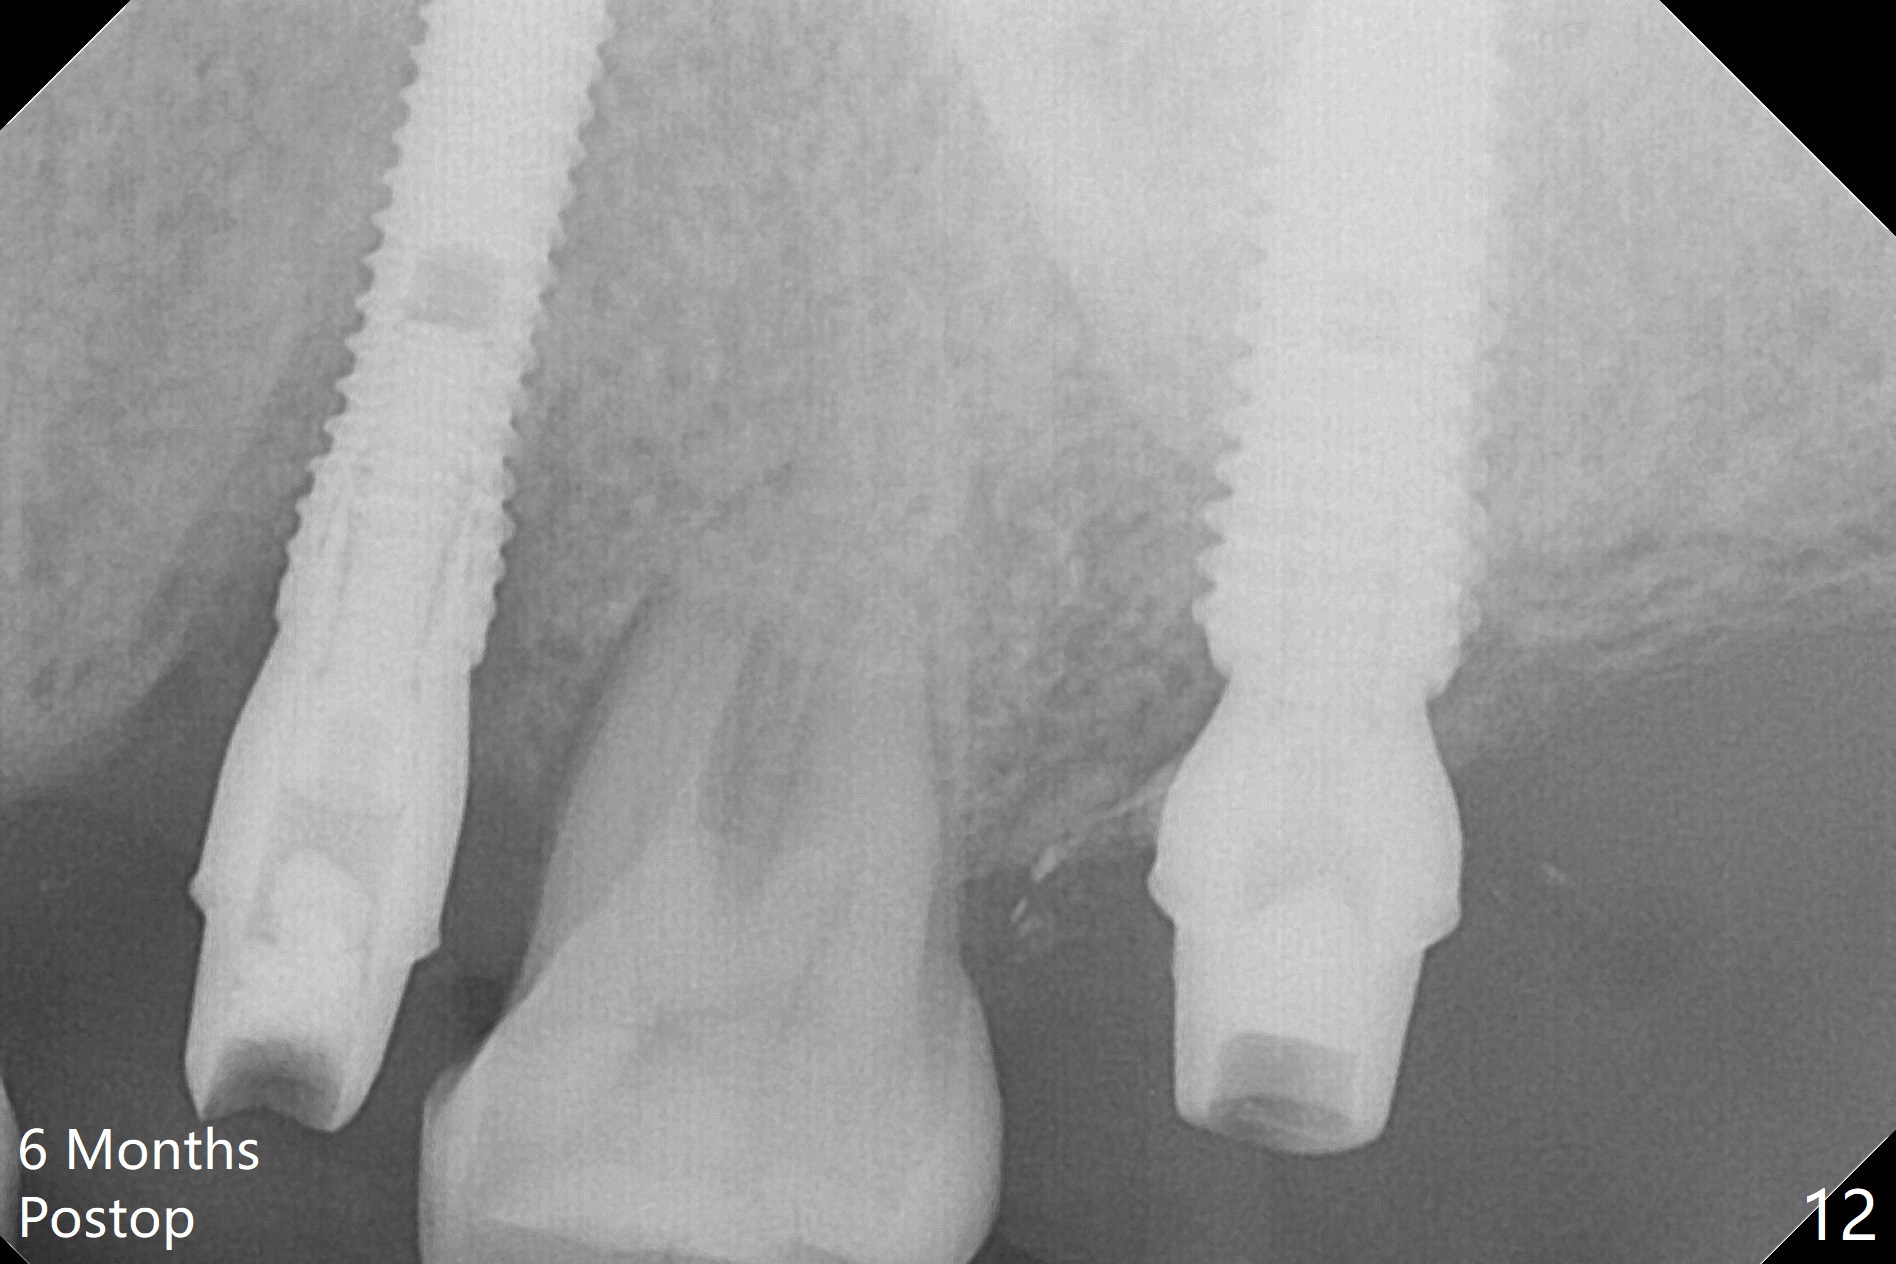

Initial osteotomy depth is 18 mm (Fig.1 green line) with 9 mm in the native bone (red line). The bone density feels to be low. There is at least 2 more mm bone apically (pink line). The depth is increased by 2 mm so that when a 3.8x15 mm implant is placed, there is 10-11 mm implant/bone contact (Fig.2 red line). There is large bony defect (Fig.3 *), which is bone grafted (Fig.4 *). Finally a longer abutment is placed (4.5x5.5(5) in Fig.4 vs. 4.5x4(5) in Fig.2,3). The 5 mm cuff does not look too long buccally (Fig.5) or palatally (Fig.6). To prevent postop buccal gingival overgrowth (2), the buccal margin of an immediate provisional is subgingival (Fig.7-9 *). Bone density between #13 and 14 appears to increase 3 months postop (Fig.10). The implant seems to be equi-crestal (Fig.11 ^). There seems to be more bone growth (i.e., decreasing gap) 6 months postop (Fig.12). Impression is taken. A crown is delivered nearly 7 months postop (08/07/2017). While there is minimal bone loss at #13 and 15 three years and 4 months post cementation, the tooth #14 and 18 are mobile (Fig.13,14).